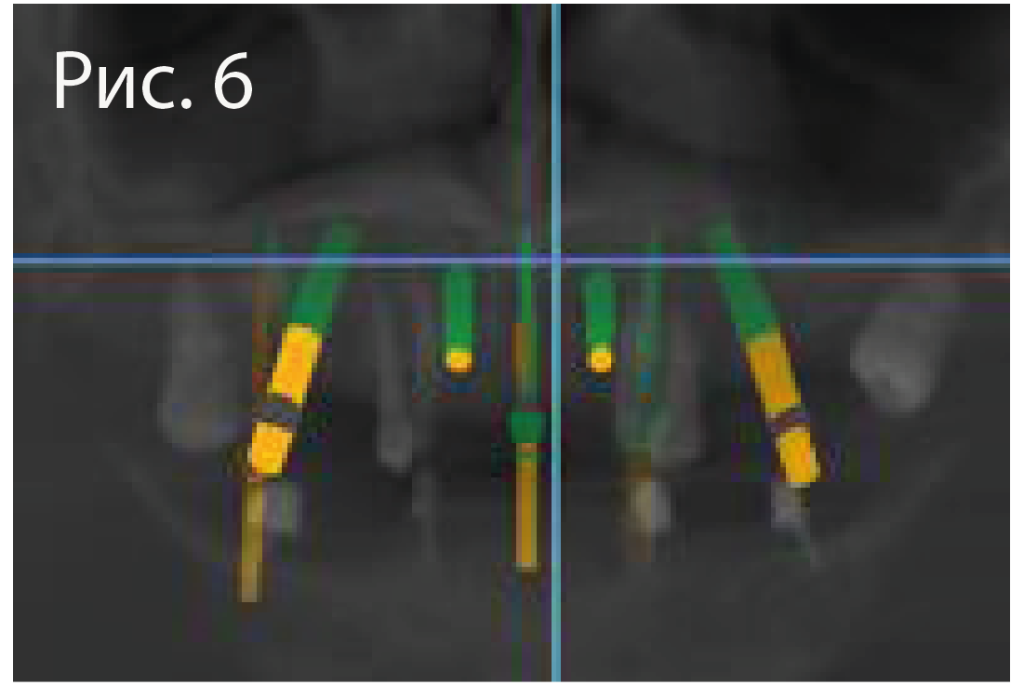

6.png

Виртуальное планирование имплантации на верхней челюсти